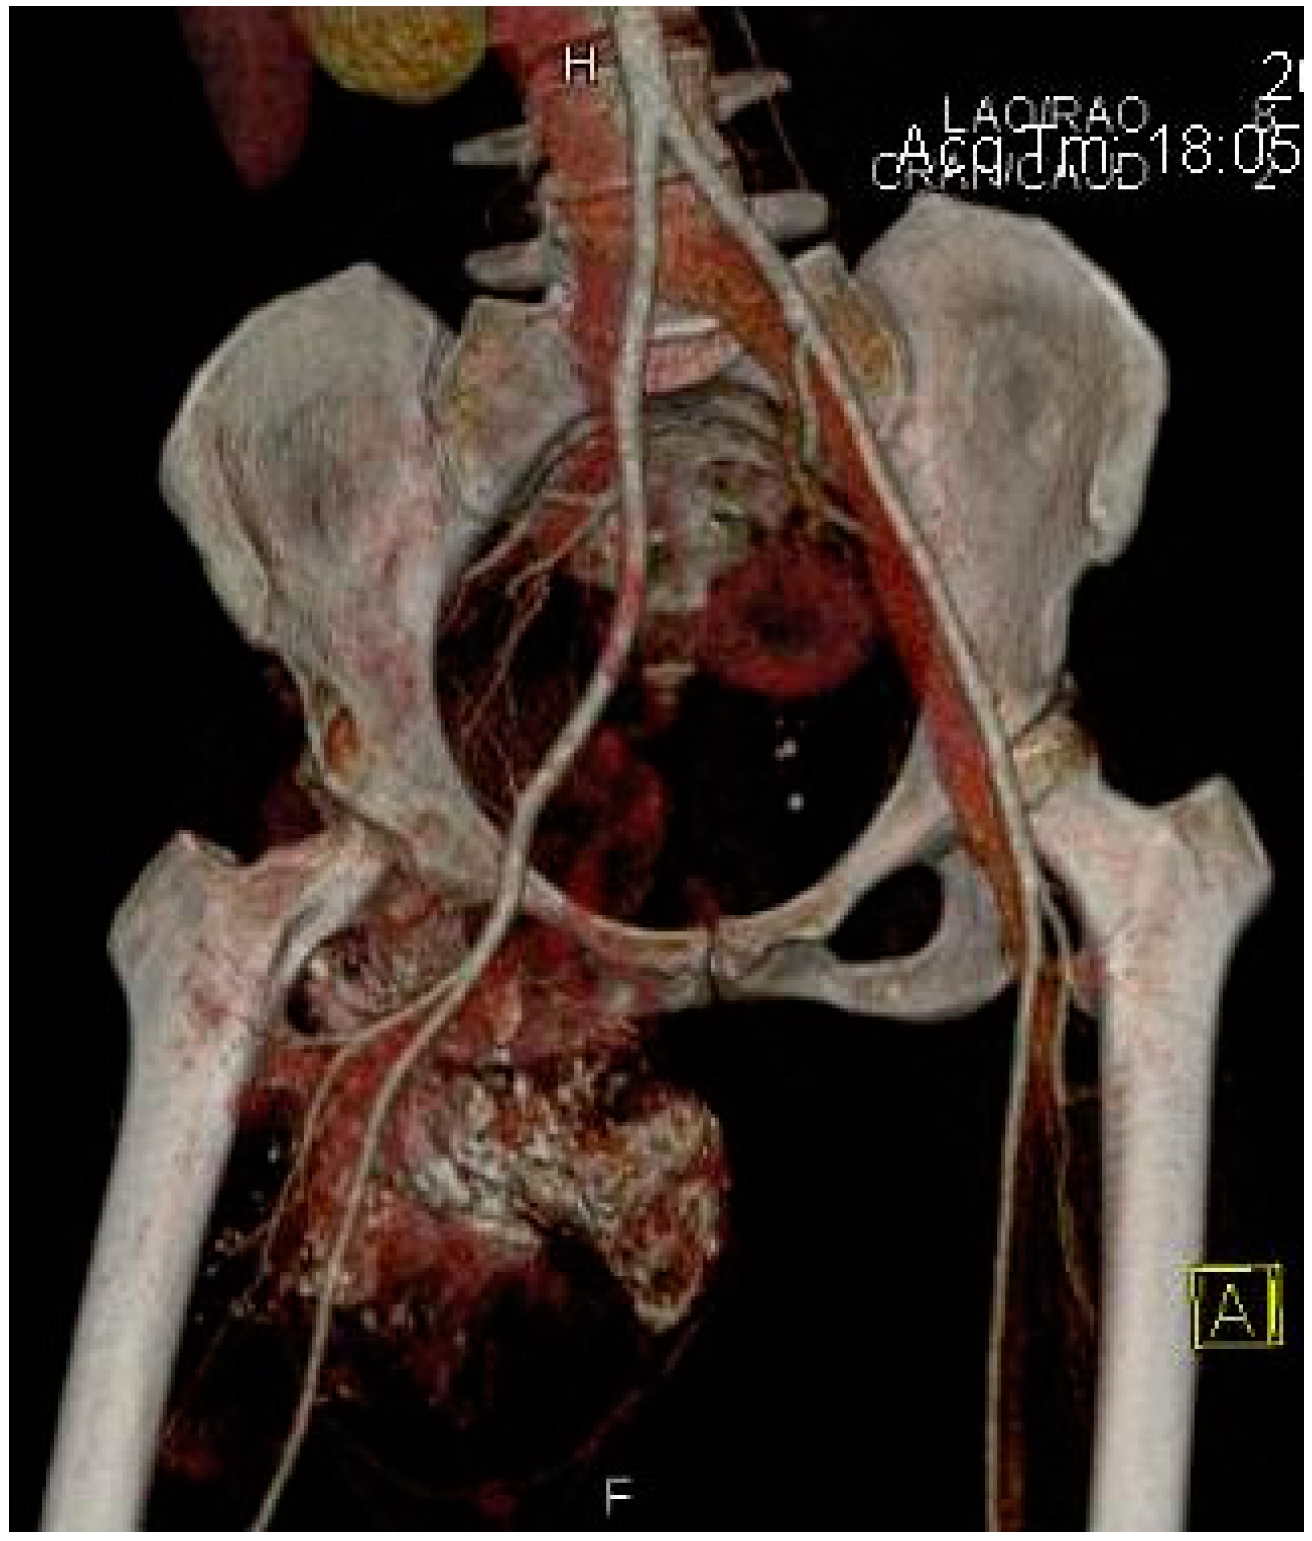

Other imaging examinations may be required. For example, a bone scan may be useful in detecting possible metastatic lesions or an Angio-CT may be requested by the oncologic surgeon, especially for deep synovial sarcomas in order to understand the relationship of the tumor with the neurovascular structures for appropriate preoperative planning (Figure 7).

Figure 7.

Angio-CT with 3D reconstruction indicating the relationship of the synovial sarcoma with the major arterial vessels and the tumoral vascularization.